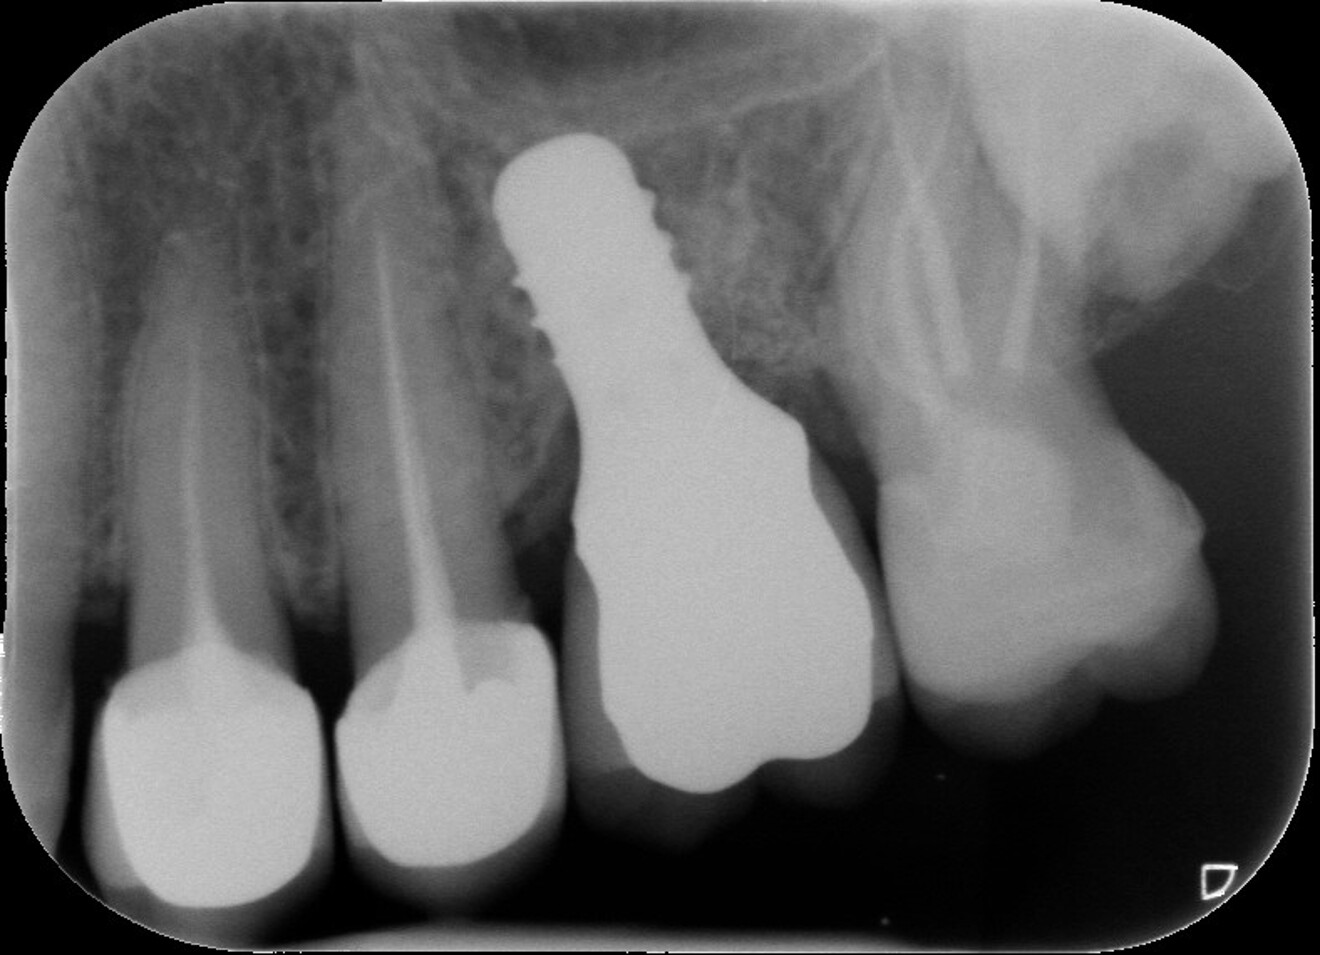

Fig. 3 : Contrôle radiographique après la finition de la prothèse.

D’un point de vue pratique, la première étape consiste à réduire les dimensions du tenon s’il occupe une grande partie de la structure coronaire, de préférence en lui donnant une forme cylindrique similaire à celle d’un tenon préfabriqué. De même, une reconstitution corono-radiculaire coulée ancrée dans plusieurs canaux doit d’abord être sectionnée jusqu’au niveau du plancher de la cavité pulpaire, afin de la traiter comme un ensemble de tenons unitaires, ce qui diminue le degré de rétention global du système. La réduction du tenon doit être effectuée avec des fraises en carbure spécialement conçues pour découper le métal, sous une irrigation abondante. Les évaluations cliniques et radiographies préliminaires sont essentielles pour planifier l’angle de coupe. La procédure doit être fréquemment vérifiée et, si nécessaire, il convient d’effectuer des contrôles radiographiques avant qu’une quantité excessive de dentine ne soit sacrifiée (Figs. 1–3).